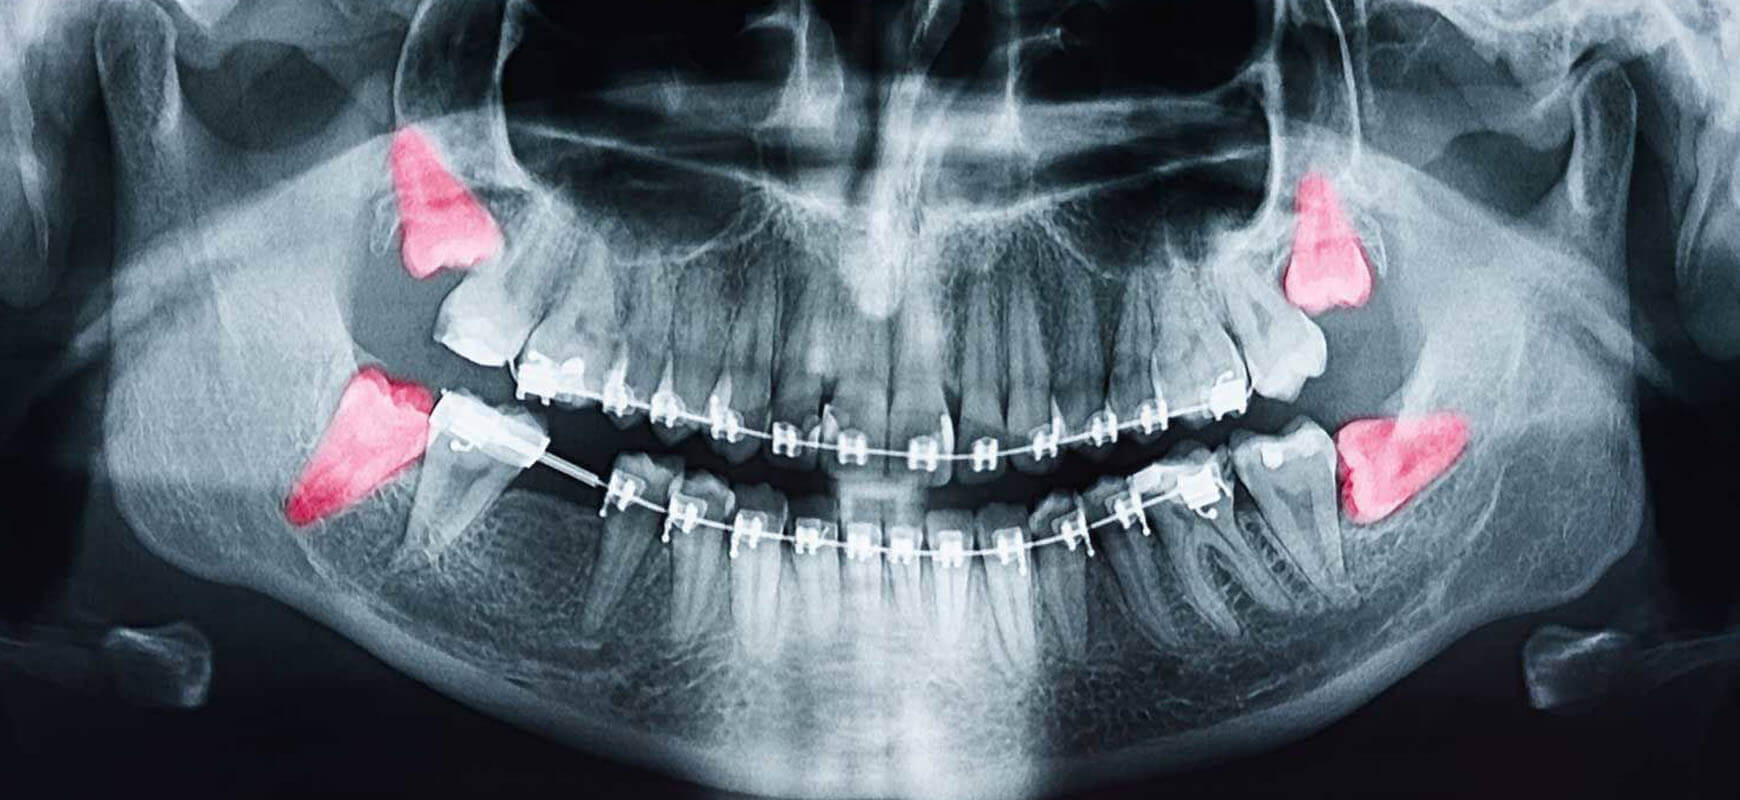

Çene içinde gömülü kalan yirmilik dişlerin cerrahi olarak çıkarılmasıdır. Lokal anestezi altında uygulanır. Ağrı, enfeksiyon veya dizilim bozukluğu yapan gömülü dişlerde gereklidir. Diş dizilimini korur, enfeksiyonu önler. İşlem tek seansta tamamlanır, iyileşme birkaç gün sürer.